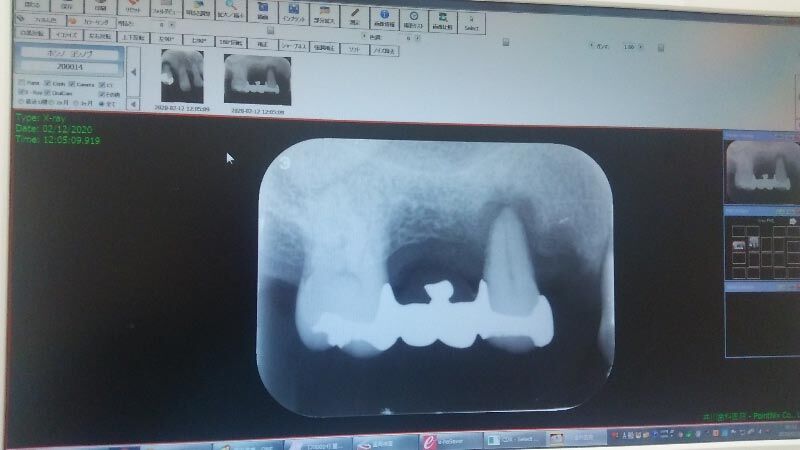

で、その抜けたところ辺りのレントゲンを撮る↓。

この写真は、右側から見ているので、写真の左側が奥歯です。

本来ならば、この写真には、4本の歯が写っていなければなりません。それを奥歯の側から1,2,3,4番と名前をつけると、1番の奥歯は健全、2番は数年前に抜けて既にない。なので1番と3番にブリッジがかかっている。

その3番ですが、あることはあるが、この歯の根がすでに浮いていて、1番からくるブリッジで支えられている状況です。この3番が浮いている影響で、根の浅い4番の歯がグラグラになり、それを抜きました。1枚目の写真の歯です。